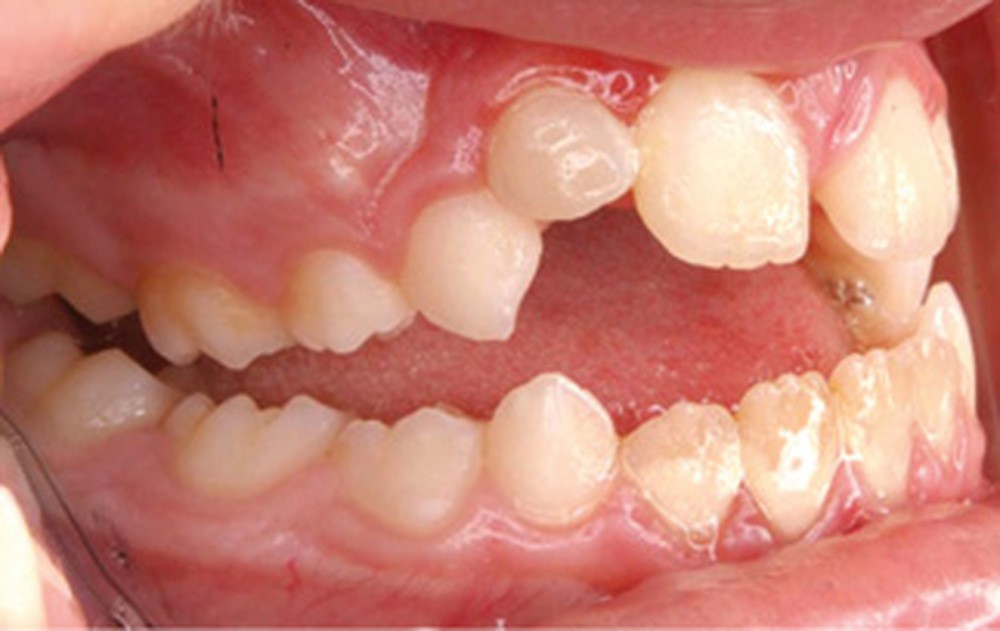

Cette patiente a été suivie dans le cadre d’un traitement interceptif alors qu’elle avait 9 ans. Elle présentait une endognathie maxillaire et une béance antérieure importante liées à des troubles fonctionnels évidents. En effet, l’examen clinique révélait une ventilation buccale exclusive, des ronflements nocturnes et une déglutition atypique. Nous avions noté à l’époque un manque de place pour l’évolution des dents définitives et un inversé d’articulé bilatéral. Les parents avaient rencontré un médecin ORL, mais avaient refusé une intervention visant à enlever les amygdales. Les deux canines maxillaires étaient incluses (fig. 1 à 6).

Le résultat de ce premier traitement a été assez spectaculaire, avec un problème transversal et une béance complètement corrigés. Les deux canines ont été mises en place sur l’arcade.